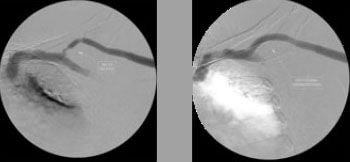

In the AVeNEW clinical study, 77 patients with stenoses in the cephalic vein arch were treated with the

Covera™ Vascular Covered Stent.

This case example demonstrates the baseline angiography showing vessel narrowing and the acute technical success with restoration of the vessel and conformability of the covered stent.